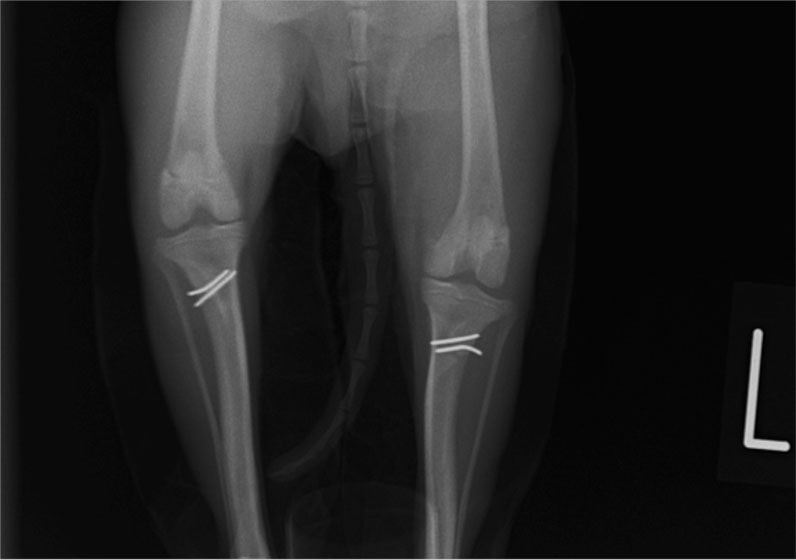

■ 症例22 ポメラニアン 1歳5か月 去勢雄

左後肢の挙上を主訴に来院した。整形学的検査、レントゲン検査より左右の膝蓋骨脱臼(左GradeⅡ〜Ⅲ、右Grade Ⅱ)を認めた。また、脛骨の前方引き出し試験の際に、引き出し兆候は認められないものの、疼痛が認められたため、前十字靭帯の損傷が疑われた。術中における、目視および関節内の操作によって、前十字靭帯の損傷や過伸展といった異常が認められなかったため、膝蓋骨脱臼の整復のみ実施した。手術手技は縫工筋及び内側広筋の解放、脛骨粗面の外側転位、滑車ブロック形造溝術、内外側関節包の縫縮を実施した。本症例は跛行もなく経過良好である。しかし、頸骨高平部の角度(TPA)が 右26.2°、左24.9°であり、解剖学的に前十字靭帯損傷のリスクが高いことから今後の経過に注意が必要である。